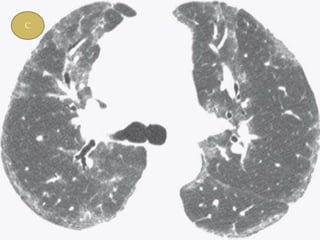

 Typical HRCT findings- GGO , irregular linear

opacity ( reticulations ), traction bronchietasis.

 GGO found in patients , changed into reticular

opacity after few years.

 Honeycombing, if present, tends to be mild

 Lower lobe predominance is common. Upper

lobe is uncommon in NSIP and should suggest

another diagnosis (chronic HP, sarcoidosis)

 Characteristic finding of NSIP is relative

sparing of the immediate subpleural lung in

dorsal region of lower lobe.